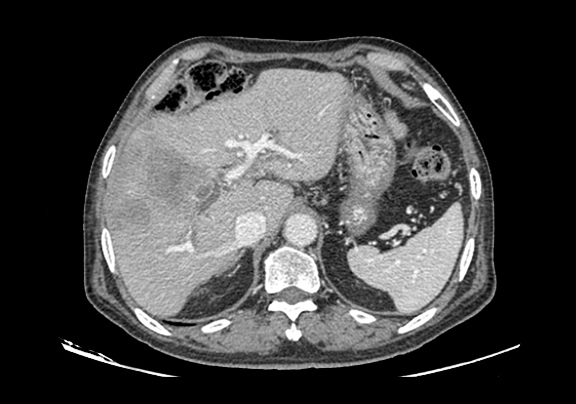

下腹部增强CT示:肝右前叶胆管细胞癌并胆管扩张可能性大。

将0.625mm双源薄层CT资料的静脉期和动脉期Dicom格式文件导入海信CAS系统。

通过调节窗宽窗位调整CT序号,对肿瘤,肝实质,胆囊,下腔静脉,肿瘤,肝动脉、门静脉及肝静脉等进行三维重建;系统自动计算肿瘤体积和肝脏体积。(图2—截图1---后链接截图2)

模拟手术操作,自动计算切除肿瘤体积。肝脏体积为1324ml,肿瘤体积为286.1ml,肿瘤体积为肝脏体积的21.6%,通过比对70-80岁正常肝脏体积为1118.08±190.14ml,通过术前模拟手术,精准判断切除后剩余肝脏体积能耐受,避免肝衰竭发生。术前手术方案的规划。

术前CT检查:

动脉期